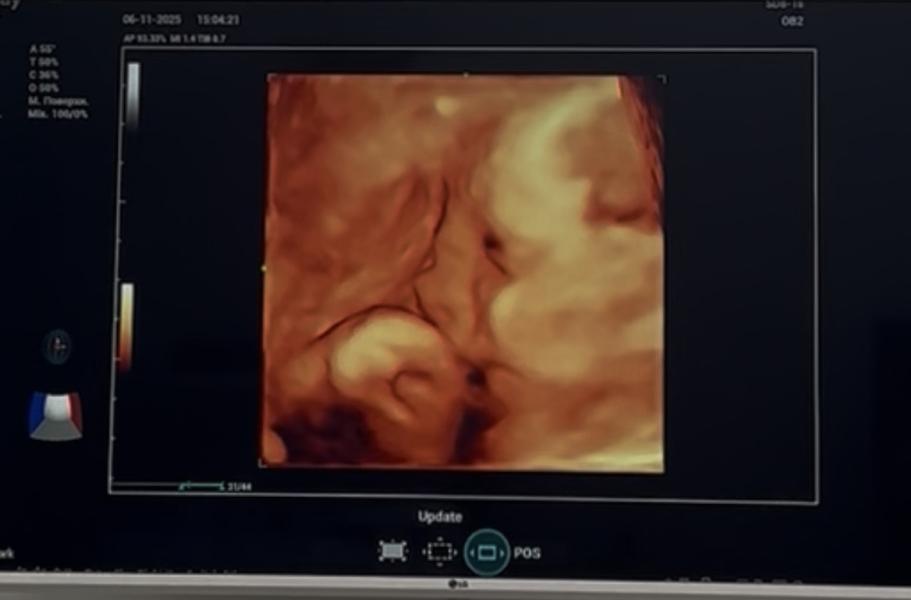

Третий скрининг в 33 недели: вес плода 2580 грамм

Третий скрининг пройден в 33.4 недели, вес набрали приличный за 2 недели🫣. Примерный вес-2580гр. Признаков ГСД нет. Мы очень счастливы 🫶🏻